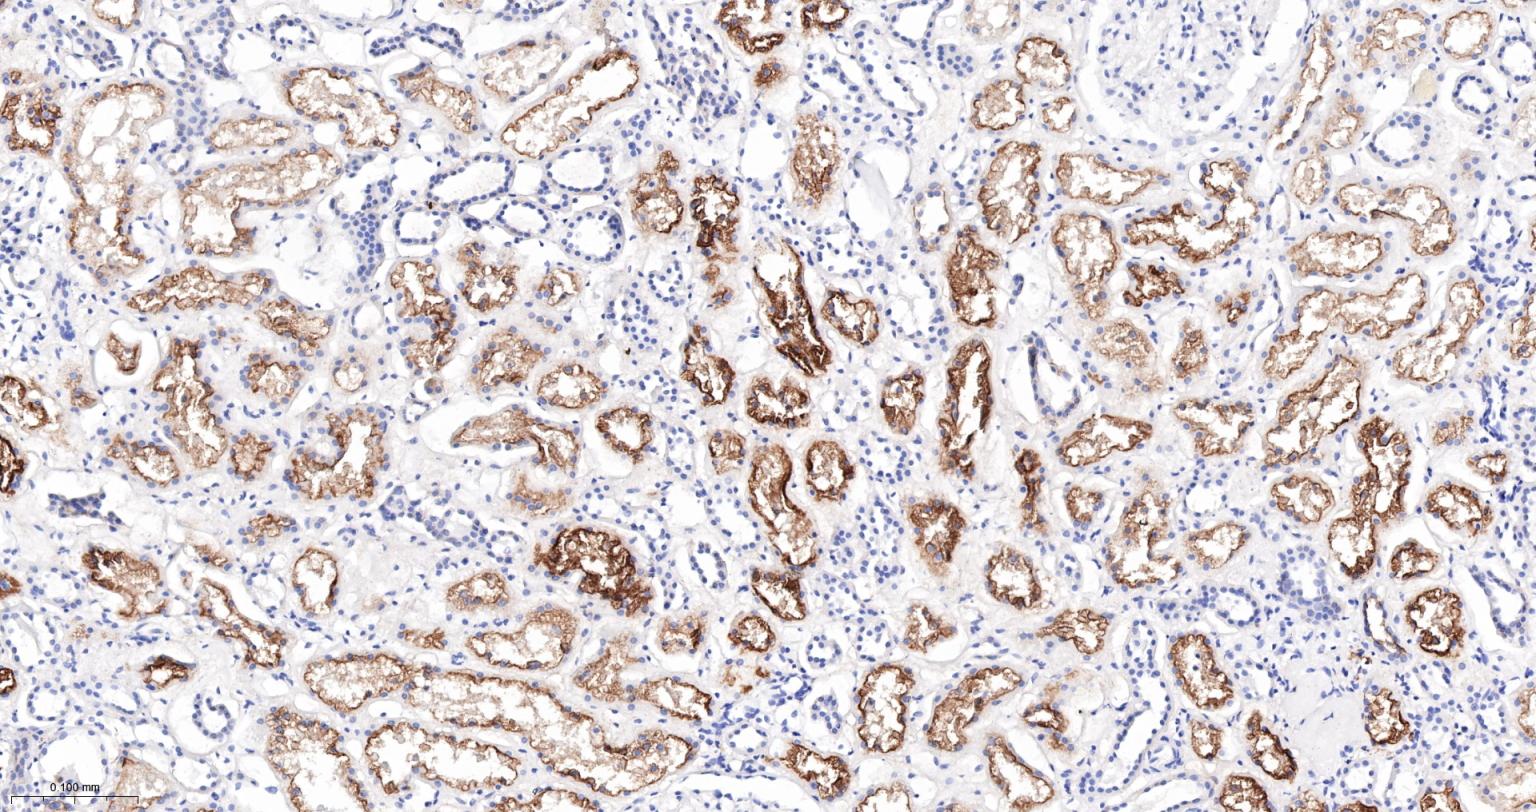

Paraformaldehyde-fixed, paraffin embedded Mouse kidney; Antigen retrieval by boiling in sodium citrate buffer (pH6.0) for 15 min; Antibody incubation with ACE Monoclonal Antibody, Unconjugated(bsm-61652R) at 1:200 overnight at 4°C, followed by conjugation to the bs-0295G-HRP and DAB (C-0010) staining.